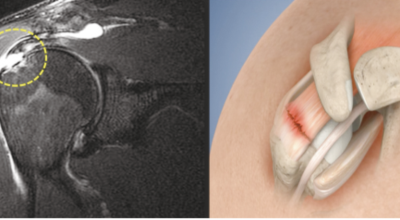

회전근개가 파열되는 경우 어깨에 통증이 생겨나게 되어요. 회전근개는 어깨 회전 운동에 영향을 줌으로 인해 팔을 들어올리는 동작에 제약이 생기기도 합니다. 이러한 증상은 오십견 증상과 비슷하기도 한데요. 수동적 움직임도 제한되는 오십견과는 달리 다른 사람의 도움을 받게 되면 팔을 들어올릴 수 있다는 차이가 있답니다.

회전근개파열은 가만히 서 있는 경우 통증이 줄어들기도 하지만 눕는 경우 통증이 더 심해지며 통증이 발생한 부분으로 돌아 눕기가 어려워 수면 장애를 동반할 수도 있죠. 그리고 어깨는 수시로 쓰이는 부위인 만큼 통증이 발생하다 보면 일상에도 큰 불편함을 줄 수 잇어 초기에 치료를 받는 것이 좋습니다.

다음 증상은 움직일 때 소리가 나는 증세입니다. 자주는 아니긴 하지만 어깨를 360도 돌릴 때 마찰음이 들리는 증상이 있답니다. 어깨를 포함한 팔의 움직임이 제한되어요. 가장 공통적인 증상이고 전반적인 움직임에 제한이 있어서 일상생활을 하는데 불편함을 호소하게 됩니다. 다음 어깨 회전근개파열 증상으로는 관절염과 탈구입니다.

상완골두 즉 상완을 구성하는 뼈가 높아져 견봉과 맞닿으면서 뼈끼리 닿아서 관절염이 될 수 있답니다. 최악의 경우 파열이 왔는데 방치하면 탈구로 이어질 수 있기 때문에 조심해야겠습니다. 세팔을 위로 뻗기가 힘듭니다. 본인 스스로가 팔을 못 들어 올리는 상태가 되는데, 다른 사람이 올려주면 올릴 수 있지만 손을 떼어버리면 힘이 빠져서 팔을 떨구게 되어요.